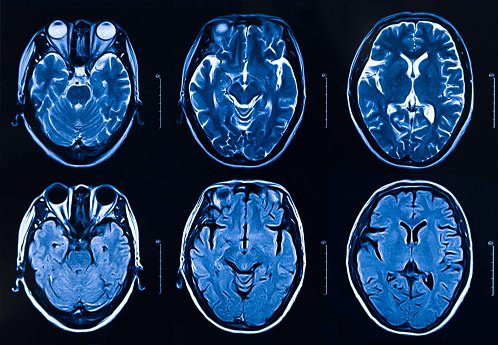

모야모야병은 양측 뇌혈관의 내벽이 두꺼워지면서 일정한 부위가 막히는 특수한 뇌혈관 질환을 의미한다. 뇌동맥 조영 영상이 아지랑이처럼 흐물흐물해지면서 뿌연 담배 연기 모양과 비슷하다고 해서 '모야모야'라고 한다.